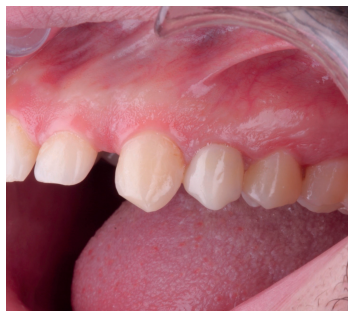

Una vez se hubo posicionado el diente 2 mm supragingival, se procedió a la ferulización con alambre de acero a los dientes adyacentes (Figuras 3 y 4) y la eliminación de cualquier tipo de oclusión, utilizando topes oclusales en los segundos molares inferiores. La ferulización se mantuvo durante dos semanas, coincidiendo con el momento de la endodoncia (Figura 5). El paciente fue citado para las revisiones periódicas y posteriormente para la rehabilitación del diente, una vez hubieron concurrido 6 semanas desde la extrusión, en las que se haya obtenido una cicatrización de los tejidos de soporte supracrestales10. En este momento, tras comprobar signos clínicos, periodontales y radiográficos saludables, se citó al paciente para el tallado y la confección mediante flujo digital (Cerec® System) de una endocorona de disilicato de litio (e.max®, Ivoclar Vivadent). El acondicionamiento de la corona se realizó con ácido fluorhídrico y silano, y para la cementación se utilizó cemento de resina (Calibra®, Dentsply Sirona).

adyacentes, tras la extrusión quirúrgica.